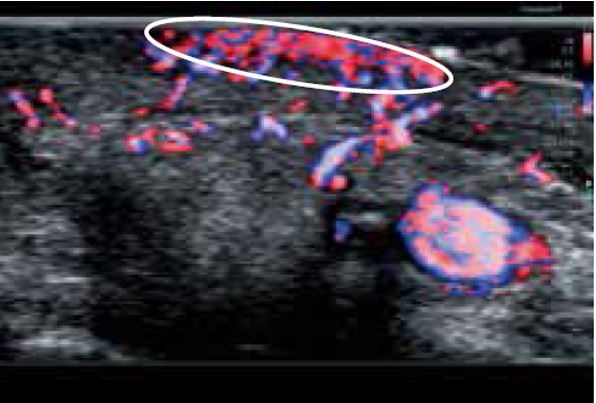

Бешихове запалення

Роздільна здатність зображення, яку забезпечує PLI-2004BX, чітко демонструє підшкірний набряк у місці ураження (рис. 6а). На кольорових зображеннях SMI (cSMI), отриманих за допомогою звичайного лінійного датчика, важко візуалізувати деталі ураження та гіперемію в епідермісі та дермі (рис. 6б). Тоді як вища чутливість cSMI надвисокочастотного датчика легко ідентифікує посилення кровотоку внаслідок сильного запалення (рис. 6в). Крім того, 3D cSMI-зображення, отримане за допомогою PLI-2004BX зі Smart Sensor 3D, одразу відображає всю судинну систему (рис. 6г). Ультрависокочастотний датчик має великий потенціал в дерматології і, як очікується, в повній мірі продемонструє свої видатні можливості з розмежування найдрібніших структур.

а) Сірошкальне зображення

б) cSMI з використанням PLT-1005BT

в) cSMI з використанням PLI-2004BX

г) cSMI зі Smart Sensor 3D з використанням PLI-2004BX

Малюнок 6. Бешихове запалення, виявлене за допомогою PLI-2004BX (24 МГц) ( а, в, г) та PLT-1005BT (12 МГц) (б).